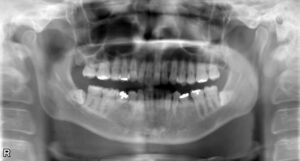

下顎小臼歯2本欠損症例(先天性欠損)

BEFORE AFTER 39歳男性/下2本欠損/インプラント埋込手術 【治療内容】 下顎第二小臼歯が左右とも先天性の欠…